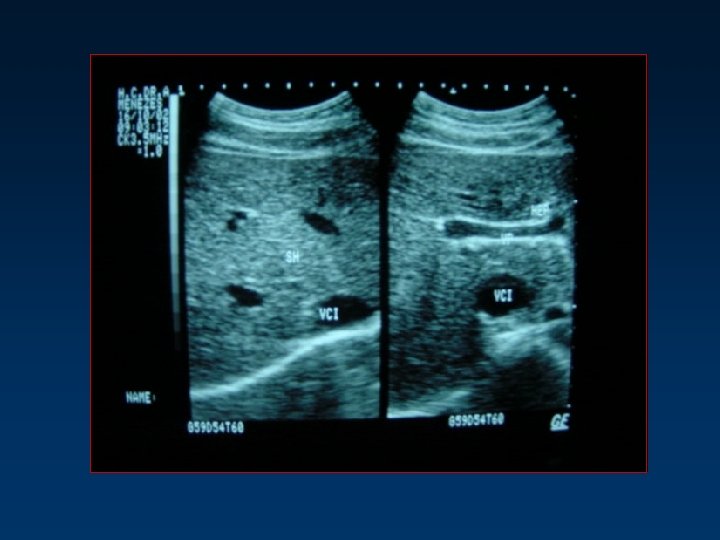

Ecografia Renal: Rins e Glândulas Supra-renais • Parênquima – rodeado pela ecogenicidade da gordura peri -renal • Ecos centrais – seio renal = gordura peri-piélica • Cálices e Bacinete – econegativos (urina) • Topografia, morfologia e dimensões • Diferenciação parênquimo-sinusal • Indiferenciação, infecção, tumores, litíase, dilatação do sistema excretor • Glândulas Supra-renais – HTA (adenomas, tumores, metástases) Sonda 3, 5 m. Hz Preparação: 6 horas de jejum